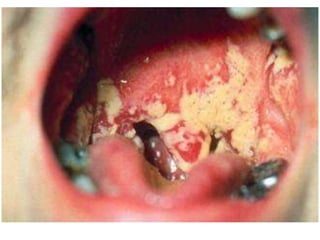

Acute membranous tonsillitis

• Stage before Acute Follicular Tonsillitis

• Exudation from crypts coalesce to form a

membrane on the surface

• Whitish membrane on medial surface which can be

easily wiped away

Acute follicular tonsillitis

• Infection ➔ Crypts ➔ Fills with purulent material

• Presents at openings of crypts as yellowish spots

• Tonsills red, swollen